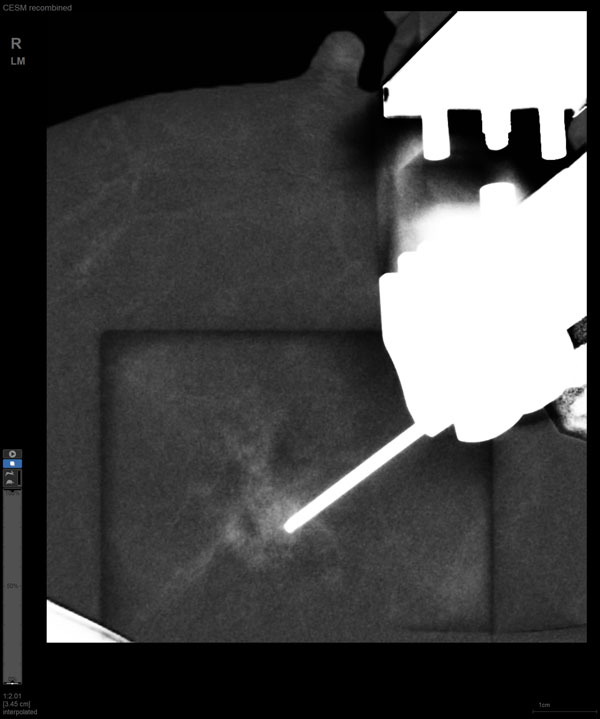

某患者增强磁共振成像MRI显示肿瘤周边有活性,中心区域有组织坏死。为得到准确的病理结果,穿刺靶区需避开肿物坏死区域。在与患者主管医生充分讨论后,放射科医生为患者行CEM引导下穿刺活检术。术中,CEM检查肿物同样显示为环形强化,巧妙避开坏死区域后,穿刺靶区选择了肿物增强早期明显强化区域,术程顺利,仅用时15分钟。术后该患者病理结果为浸润性导管癌Ⅱ级。

CEM引导下穿刺